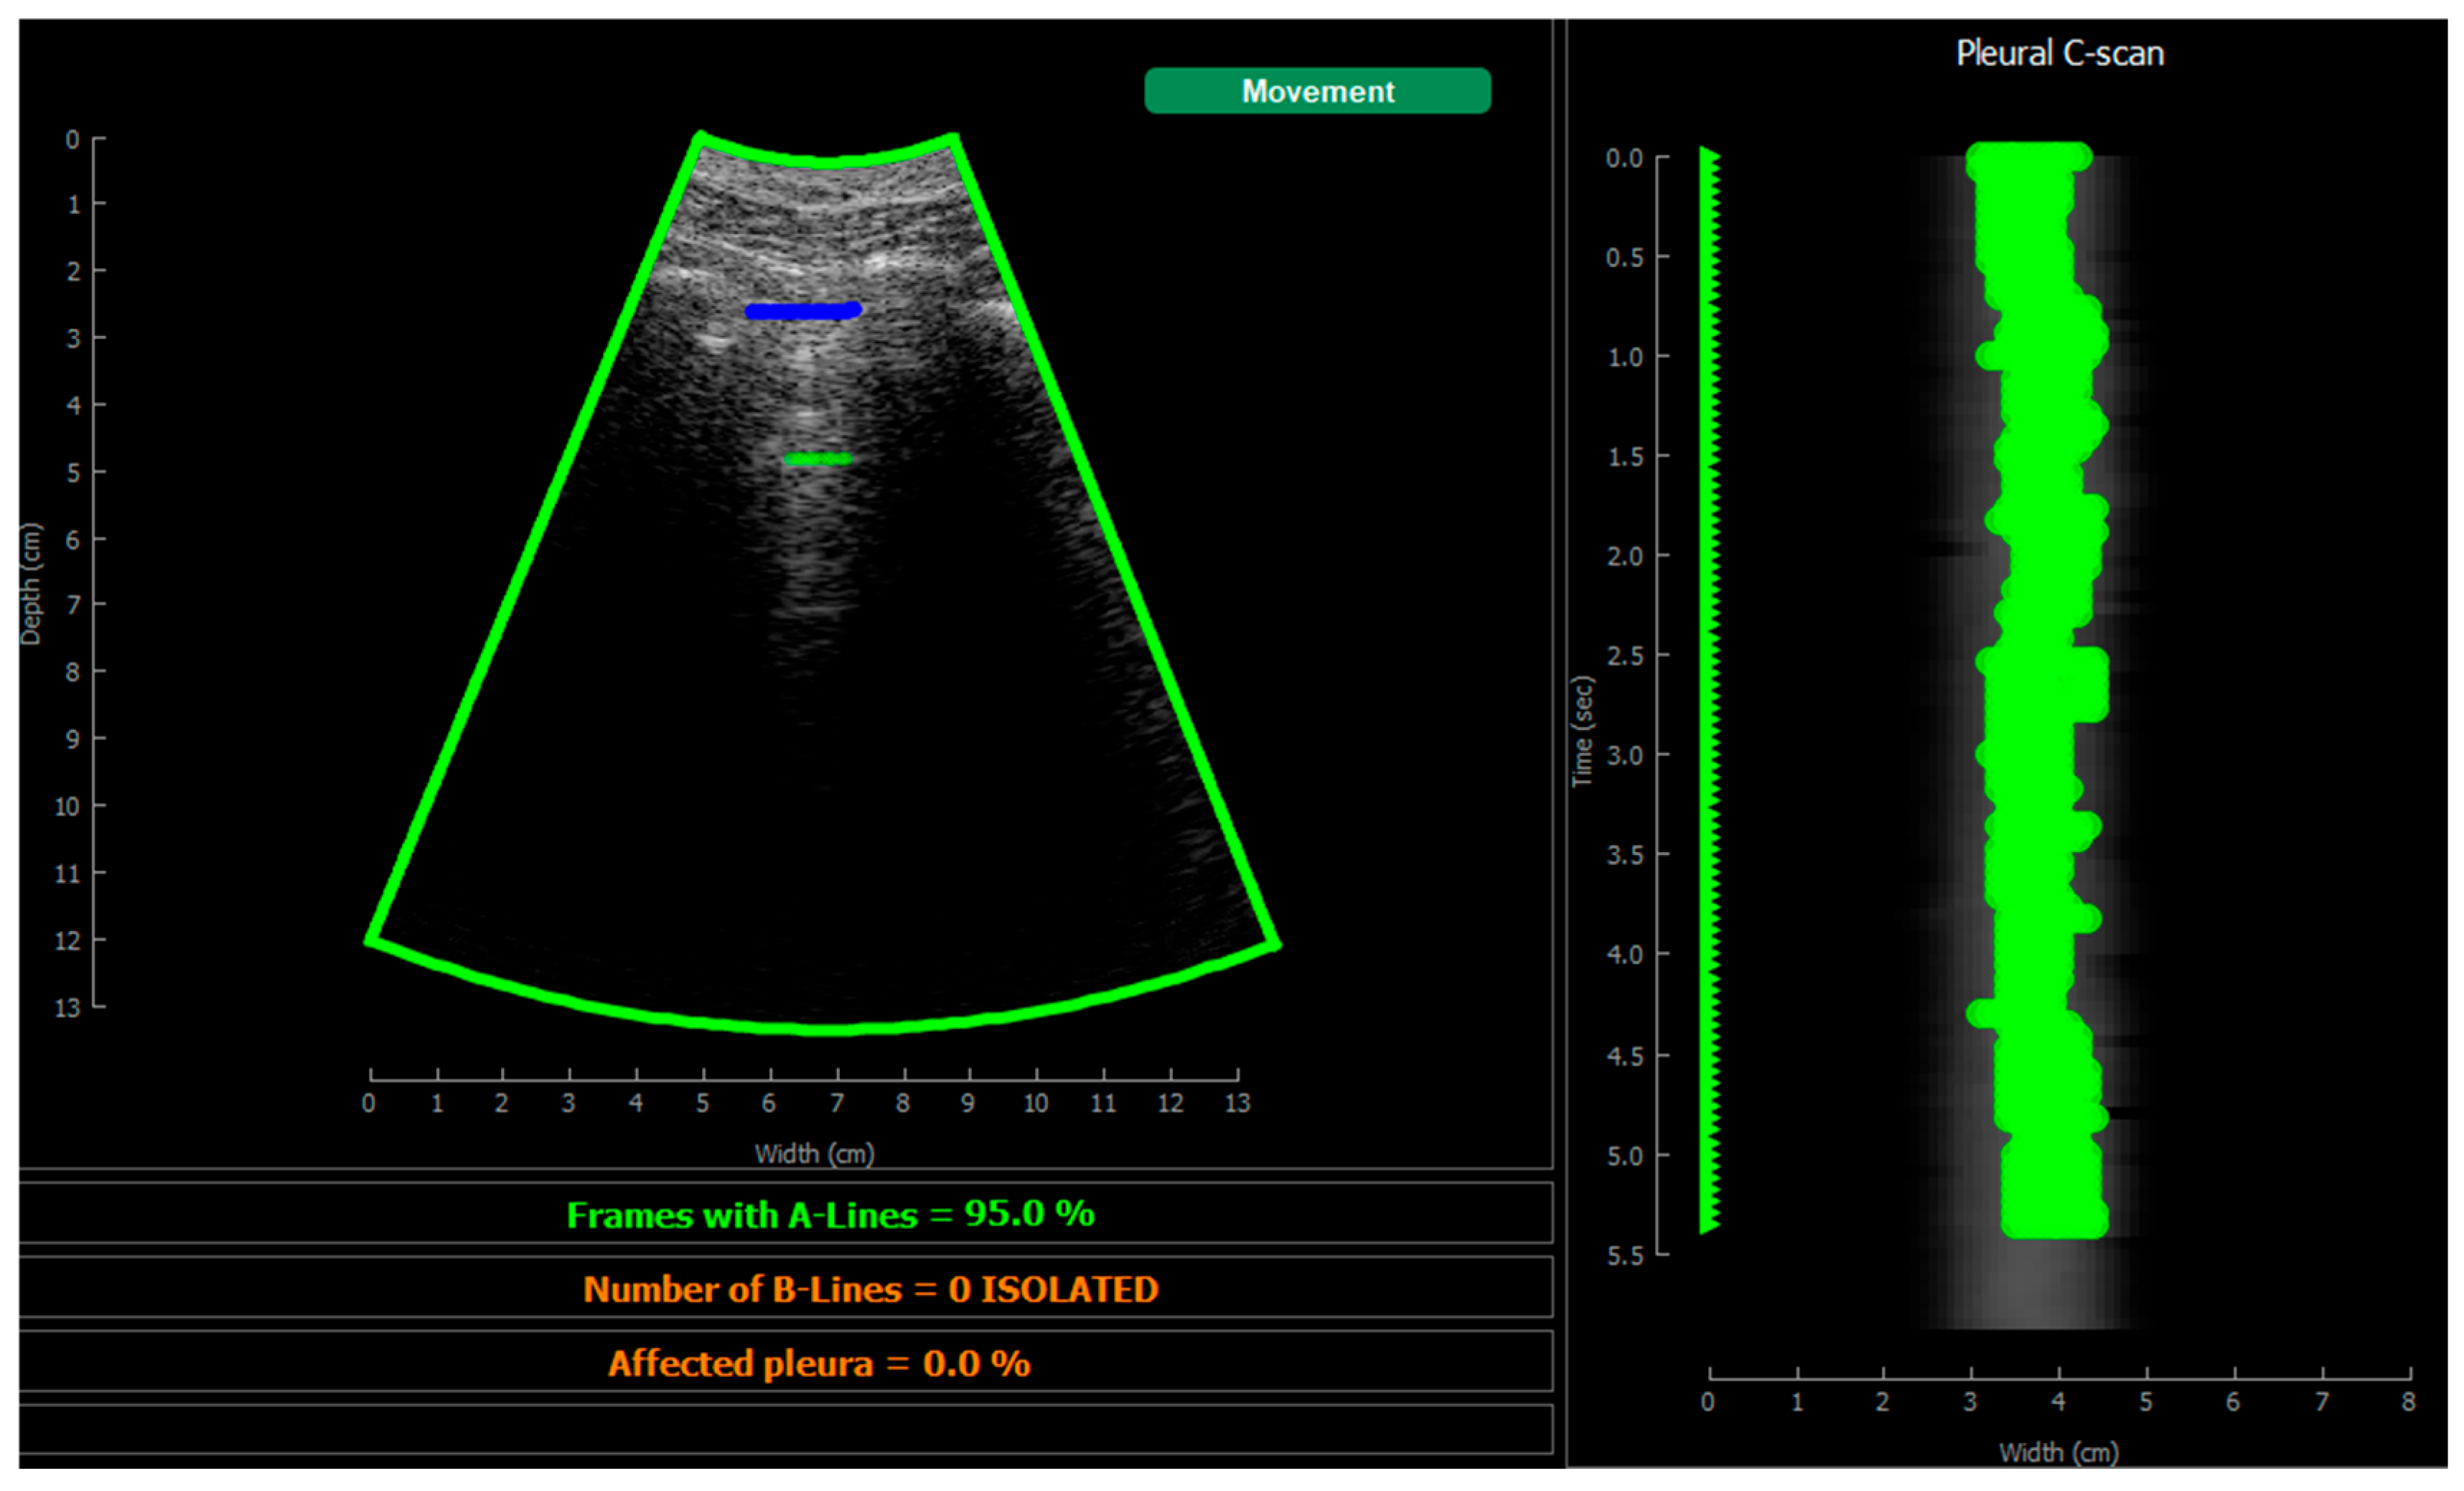

2.5.4. Visualization

3. Results

3.2. Real-Time Implementation Results